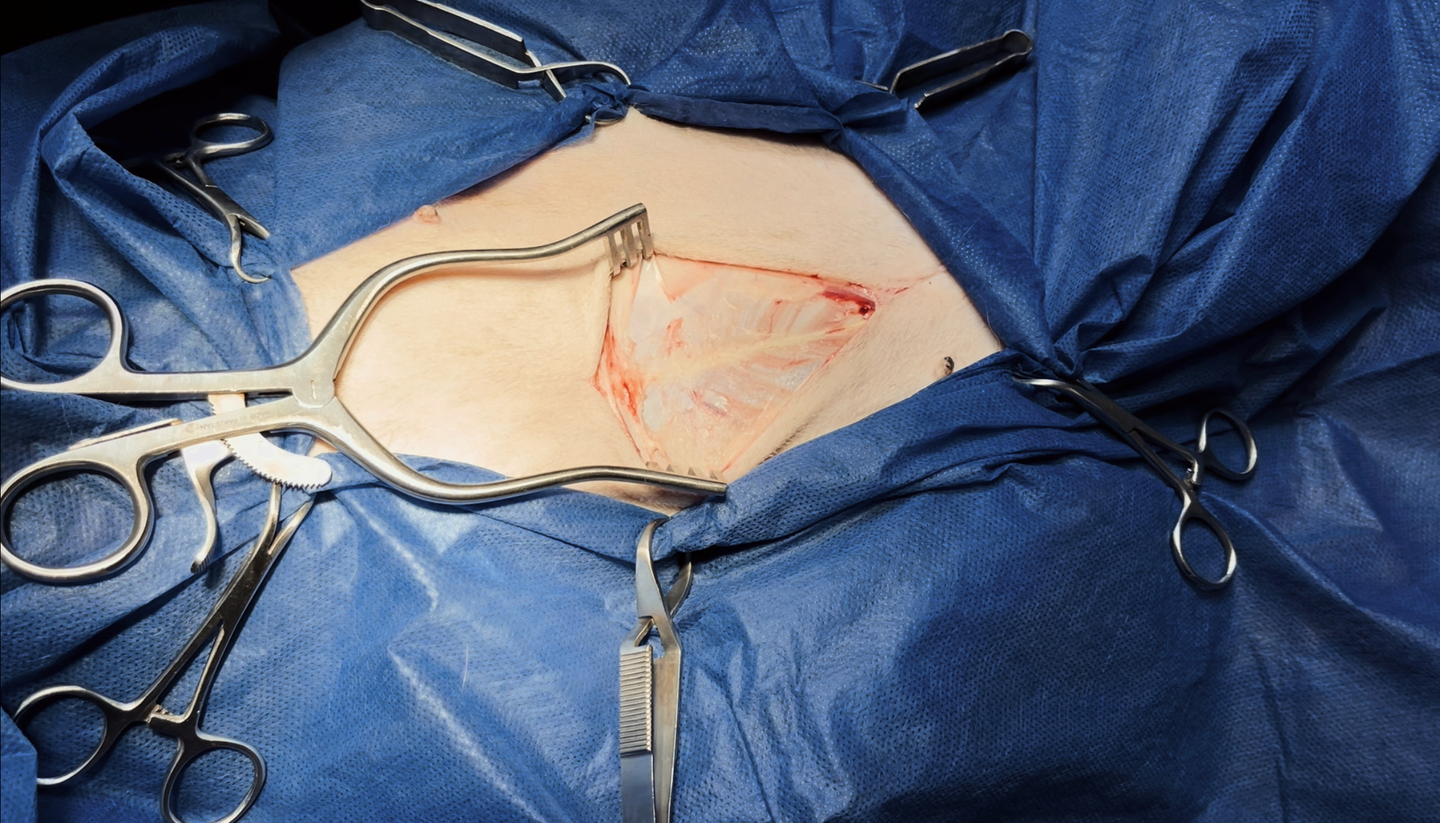

Surgery

The standard of treatment for splenic hemangiosarcoma's that have not yet metastasized to the lungs consists of surgery to remove the measurable (bulky or visible) disease followed by chemotherapy to delay the progression of metastatic disease